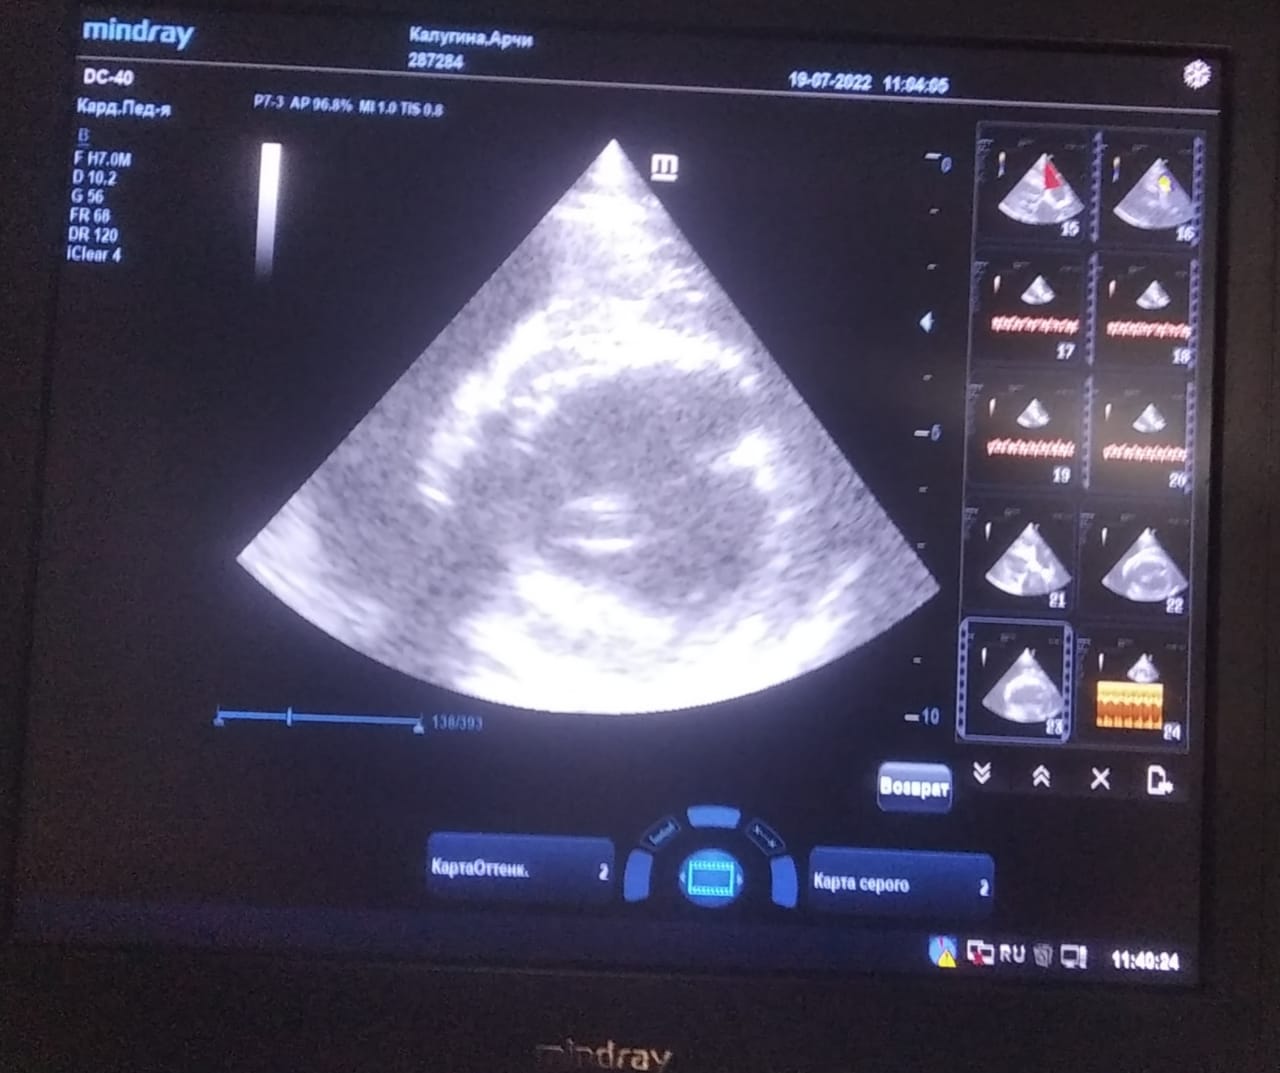

Анализы Арчи. Сердца и легких

Вложения

IMG-20220719-WA0100.jpg

IMG-20220719-WA0102.jpg

IMG-20220719-WA0104.jpg

IMG-20220719-WA0103.jpg

IMG-20220719-WA0105.jpg